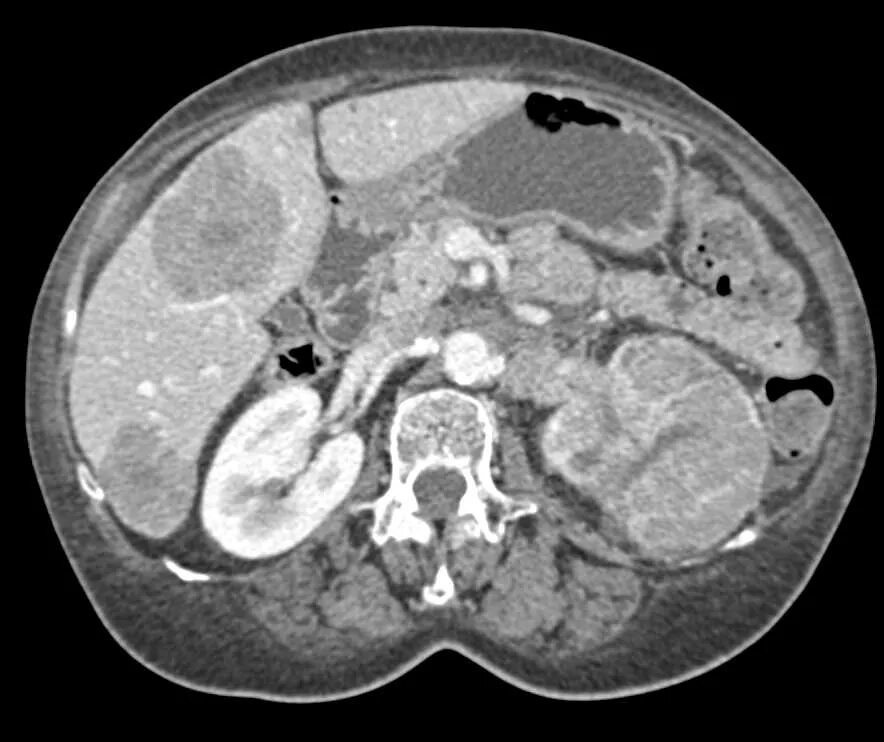

Рак почки метастазы прогноз